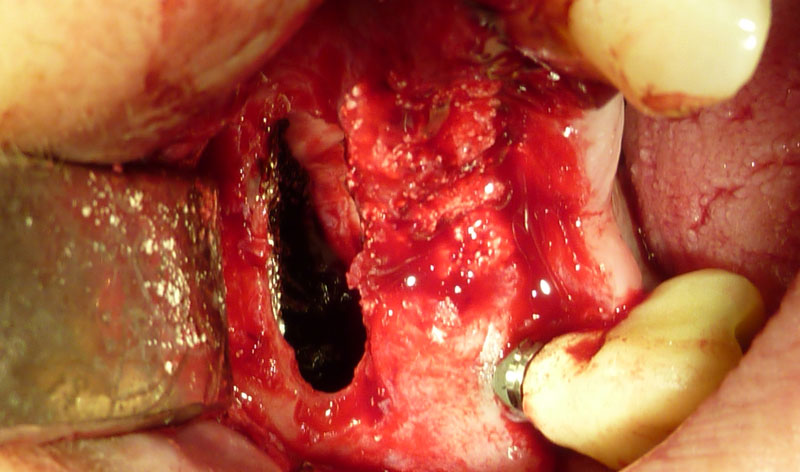

Procedimiento: se realiza una incisión en la encía, se aborda el hueso maxilar superior realizando una pequeña apertura en el margen externo del maxilar, y se introduce un cemento formado por el propio hueso y sangre del paciente, y un material óseo conductor, que proporciona una serie de condiciones básicas para la formación de hueso.

Una vez realizada la intervención, en algunos casos se pueden colocar los implantes a la misma vez y en otros, es necesario esperar seis meses para que el material óseo forme un hueso con buena calidad que asegure el éxito de los implantes.